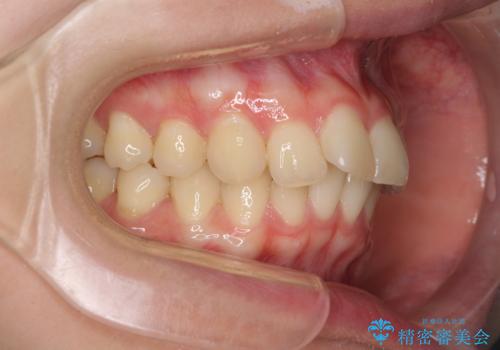

- 前歯2本が飛び出してることを気にして来院された患者様です。

全体的に黄ばんだ歯の色も気になるとのことで、マウスピース矯正により飛び出した前歯を治しつつ、ホームホワイトニングを併用して黄ばみを解消していくこととしました。

歯と歯の間を削ることで、飛び出した前歯が引っ込み、スッキリとした口元となりました。